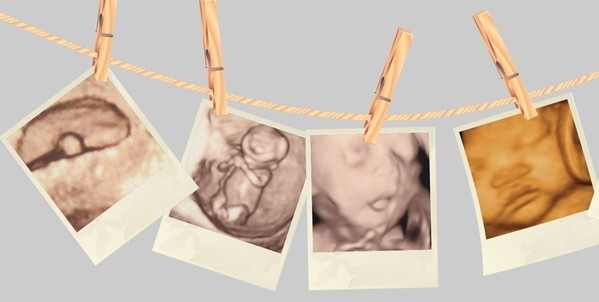

四维彩超的全称为四维彩色超声诊断仪,是目前世界上先进的彩色超声设备。由于四维彩超能够表面成像,胎儿的唇腭裂、四肢发育畸形、脑膜膨出、脊柱裂、腹壁裂等先天畸形能更清晰地查出来。四维彩超的诊断资料也有利于医师检查胎儿的发育情况,筛查先天疾病,这是主要的。

福州台江医院医师表示,妊娠后22周-28周可以做四维彩超,时间在怀孕24周-26周,因为胎儿24周左右时正是大脑突飞猛进的发育时期,这个时期的胎宝宝结构已经形成,宝宝的大小及羊水适中,在宫内的活动空间较大,胎儿骨骼回声影响比较小,图像也比较清晰,适合做胎儿畸形筛查。

四维彩超可多方面的应用,能够显示宫内胎儿的实时动态活动图像,或者其它人体内脏器官的实时活动图像。

“4D”是“四维”的缩写。第四维是指时间这个矢量。对于超声学来说,4D超声技术是新近发展的技术,也是GE公司的技术。4D超声技术就是采用3D超声图像加上时间维度参数。该革命性的技术能够实时获取三维图像,超越了传统超声的限制。

它提供了包括腹部、血管、小器官、产科、妇科、泌尿科、新生儿和儿科等多领域的多方面的应用。其结果是:能够显示未出生的宝宝的实时动态活动图像,或者其它人体内脏器官的实时活动图像。